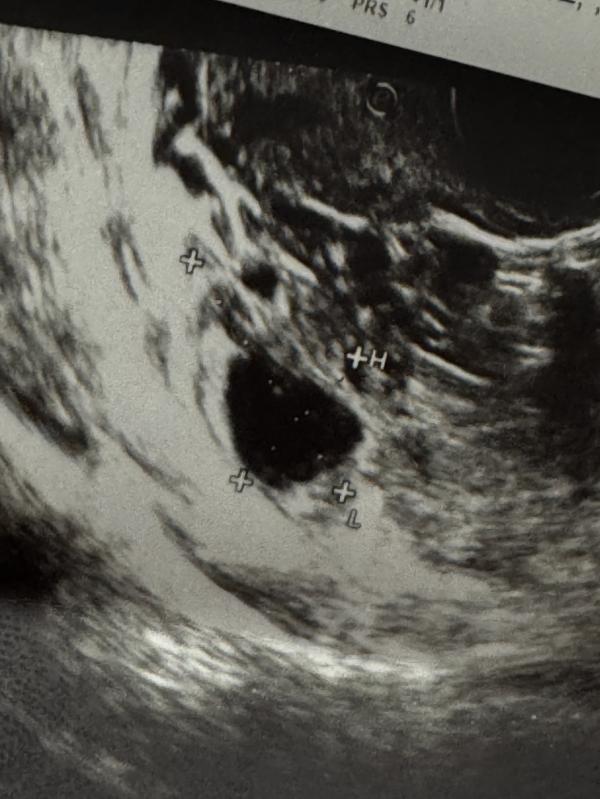

Хелп! Как вы думаете на фото фолликул несовулировавший или все таки желтое тело? 🧐

Скорее ЖТ, чем фолликул…